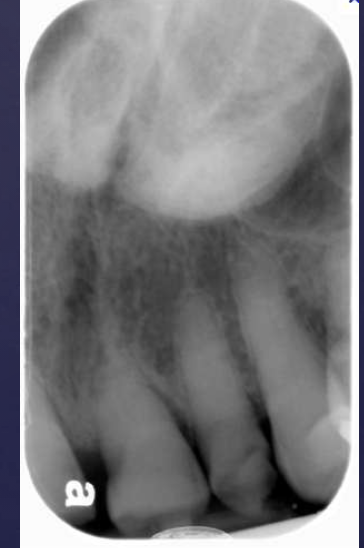

describe what’s occurring in this radiograph

pericoronal/mural; impacted tooth

displacement of #32 + IAN

osseous expansion

thinning of cortices